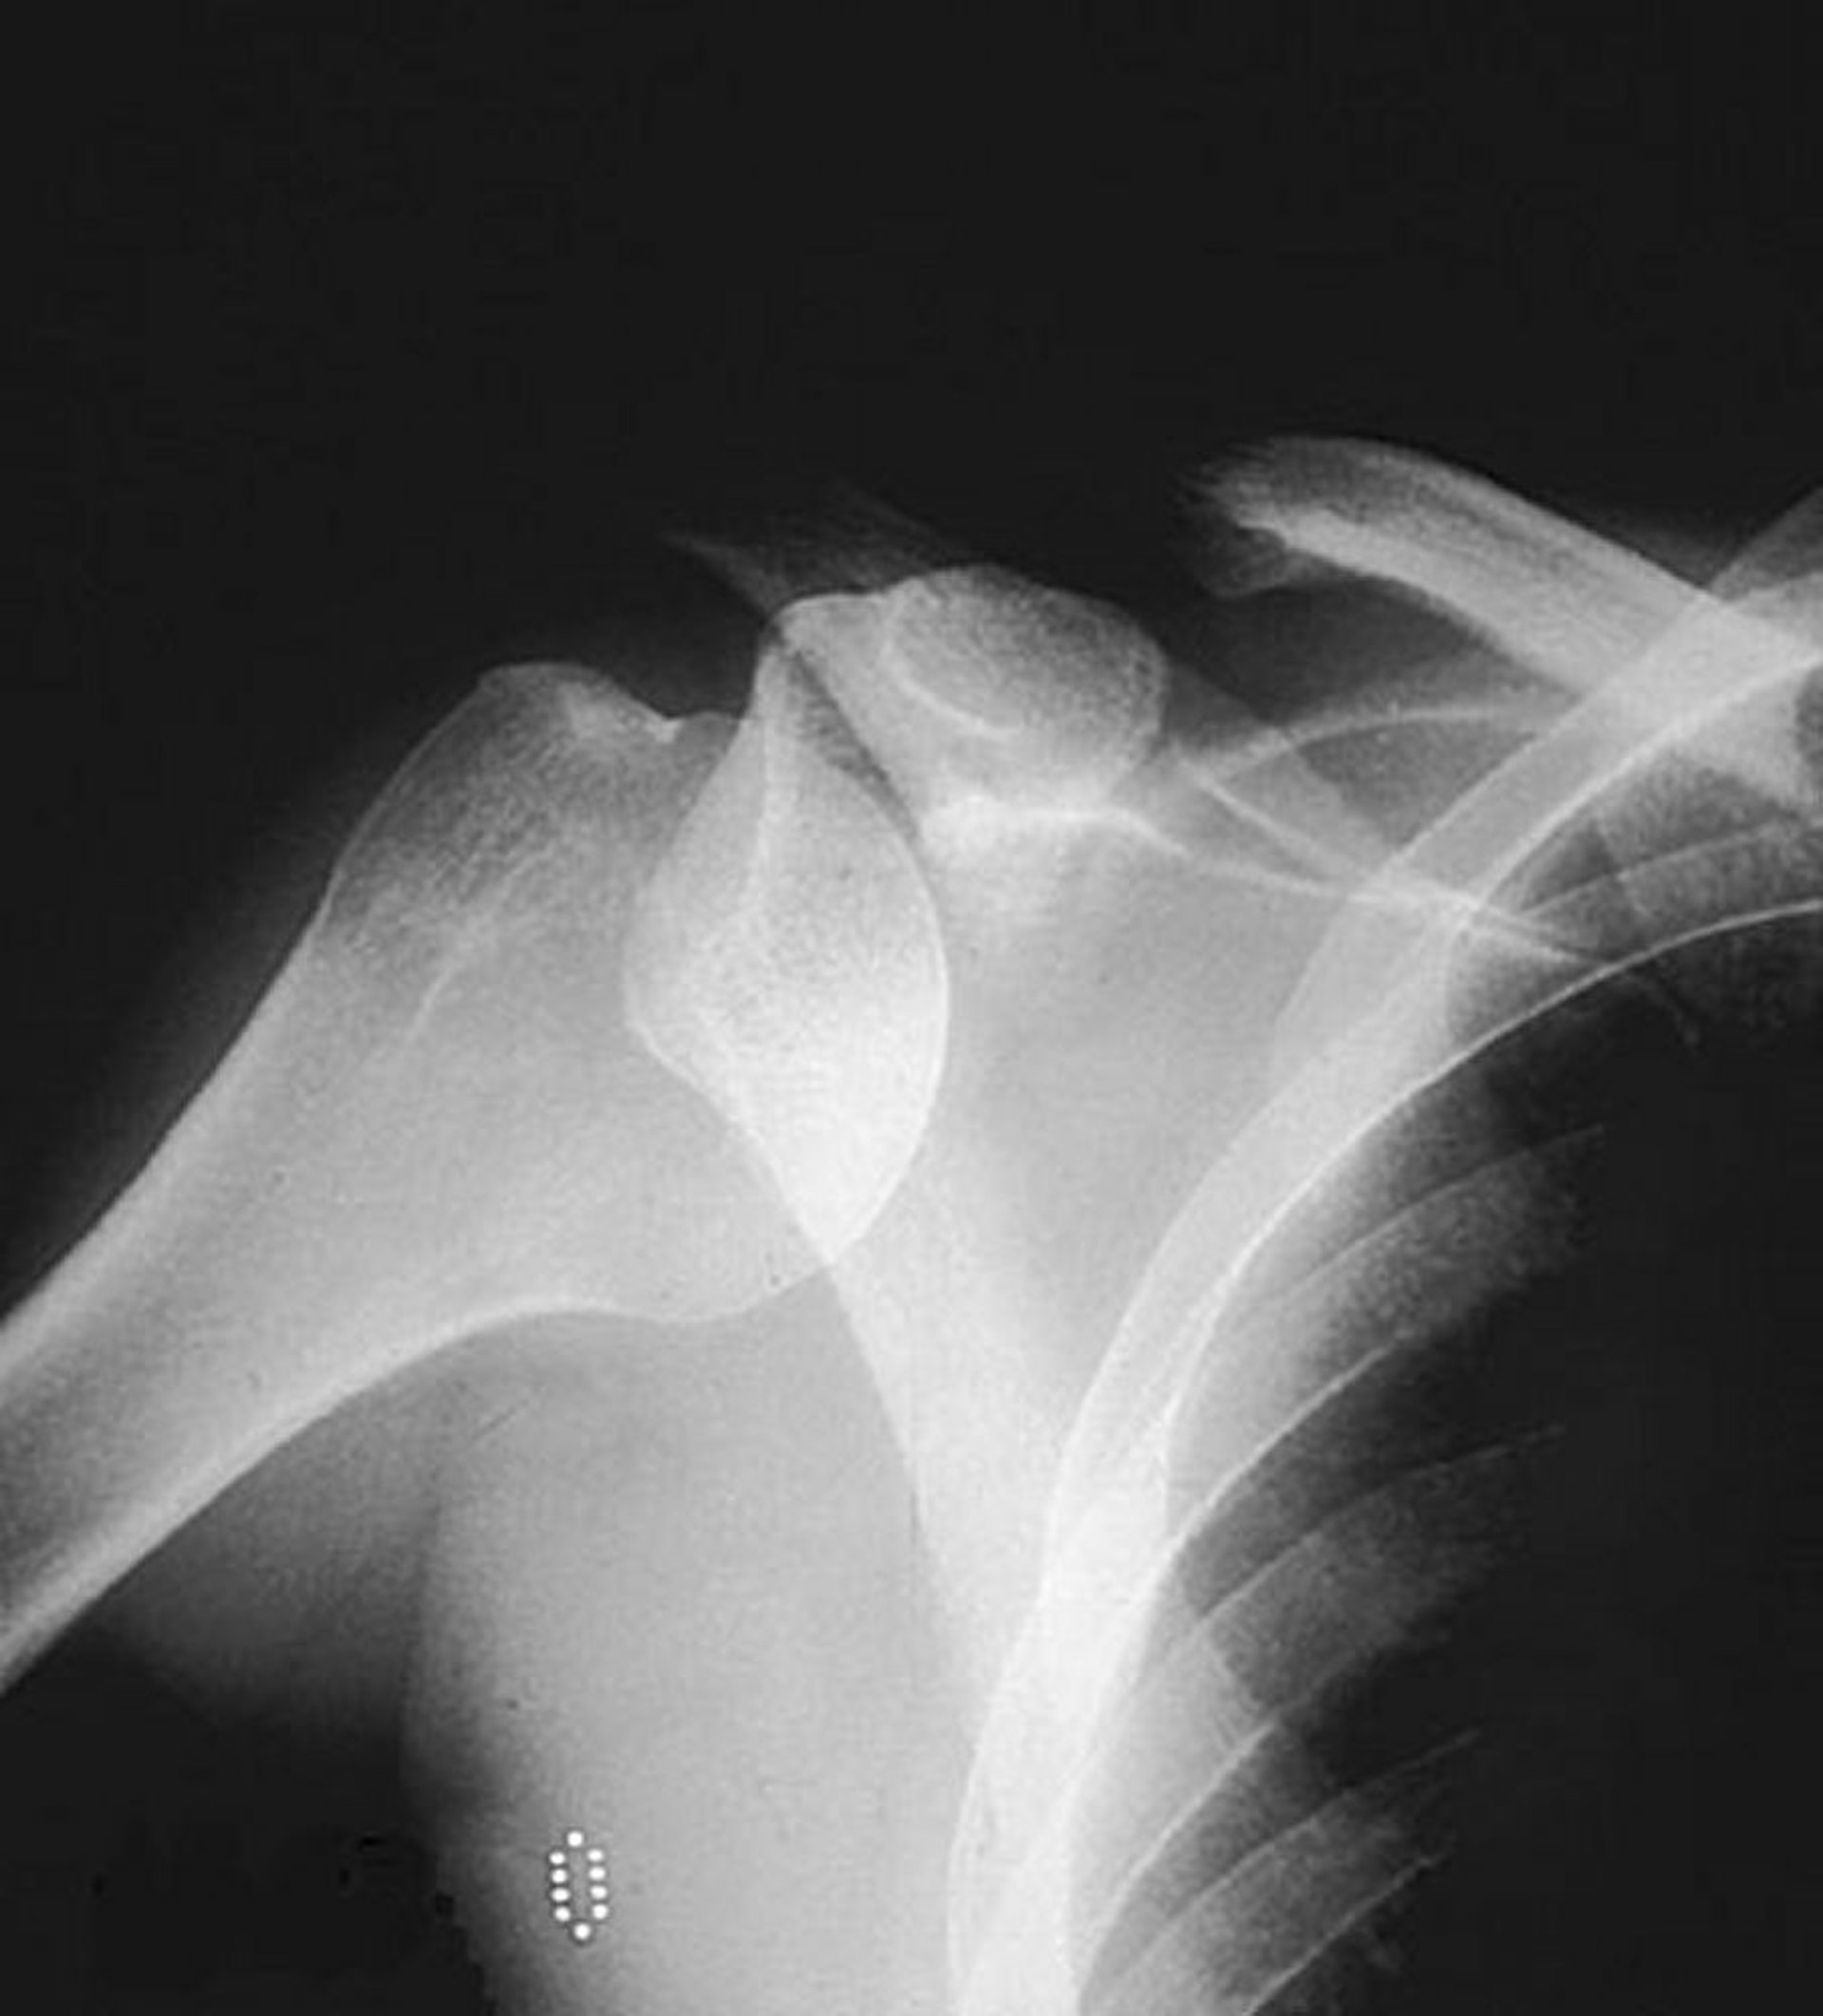

肩甲上腕関節(肩関節)前方脱臼

単純X線の前後像により関節窩内の通常の位置から外れた上腕骨頭が示され,前方脱臼が示唆される。